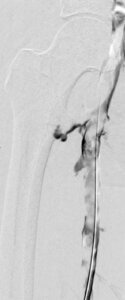

Initial Venogram

Extensive thrombus throughout the left superficial femoral vein into the pelvis.